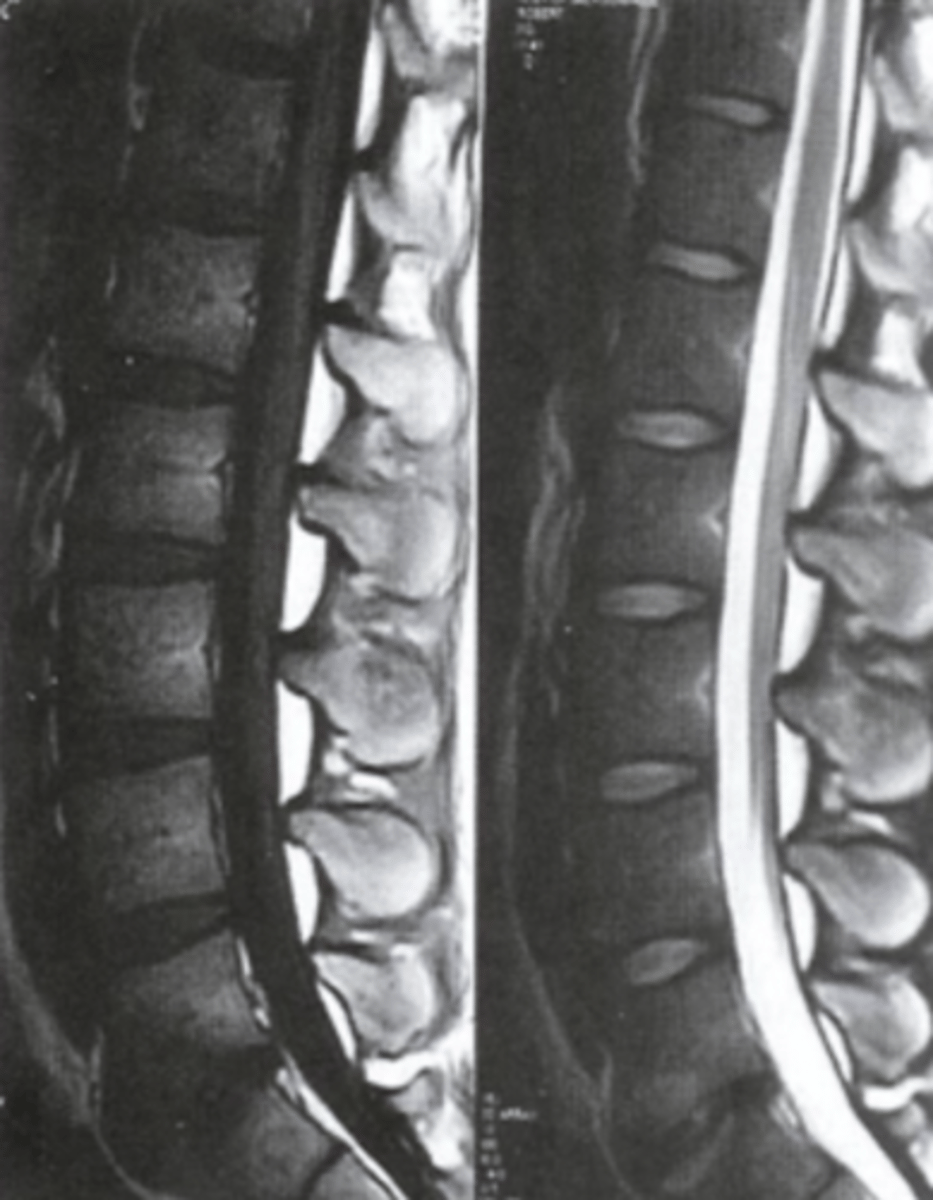

Supraspinatus muscle

What is number 1?

Pec major

What is number 2?

Glenoid

What is number 3?

Acromion

What is number 4?

Humeral Head

What is number 5?

Deltoid

What is number 6?

Biceps Long Head

What is number 7?